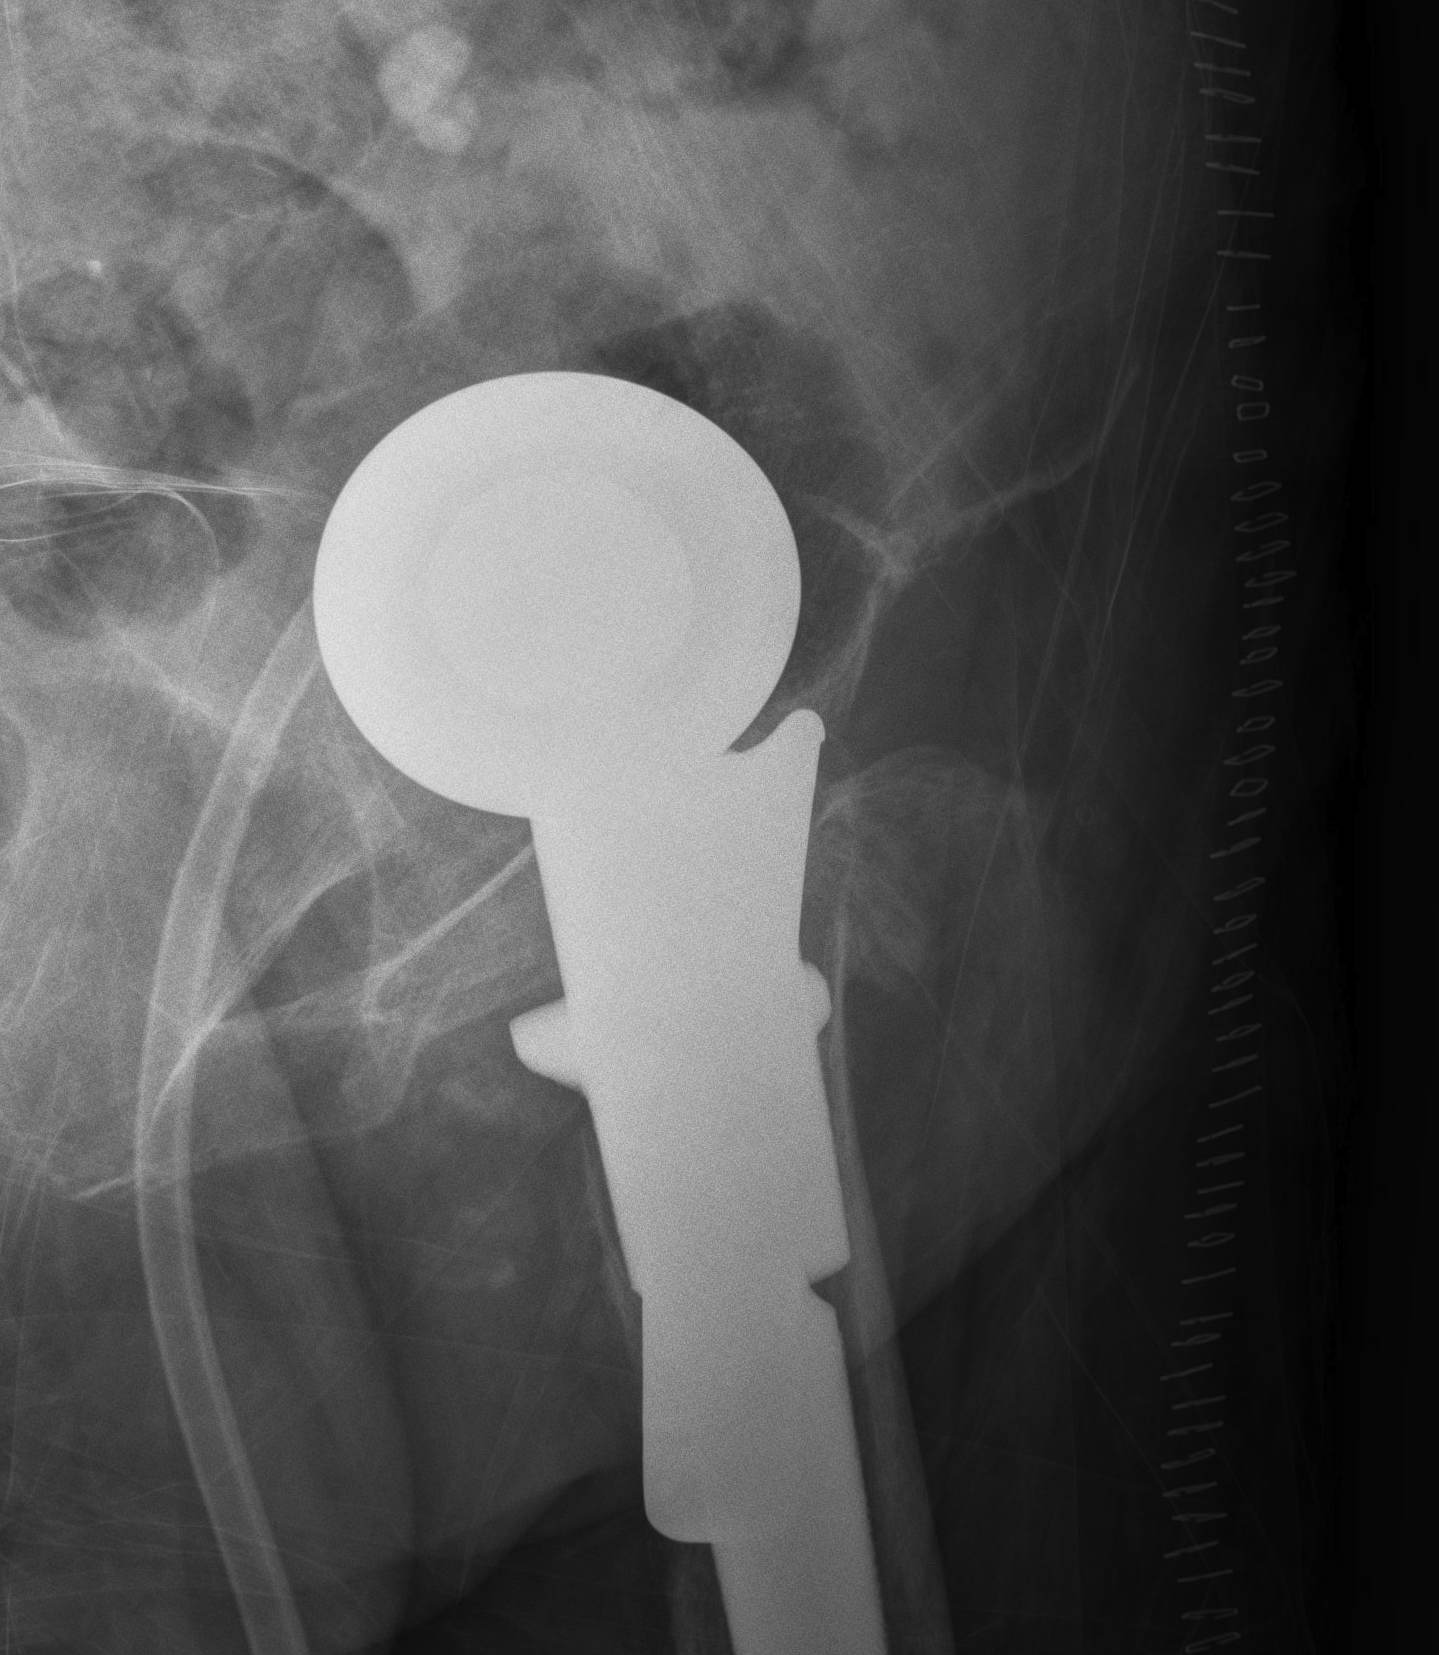

Bipolar modular

Concept

- second articulation between inner smaller head and polyethylene liner

- reduce wears on acetabulum

- improved function and less pain

- may reduce dislocation

- may have better ROM

Issues

- higher cost

- may need open reduction in dislocation if femoral head disassociates from socket

- loss of motion interface / becomes unipolar

Cemented unipolar hemiathroplasty Uncemented bipolar hemiarthroplasty